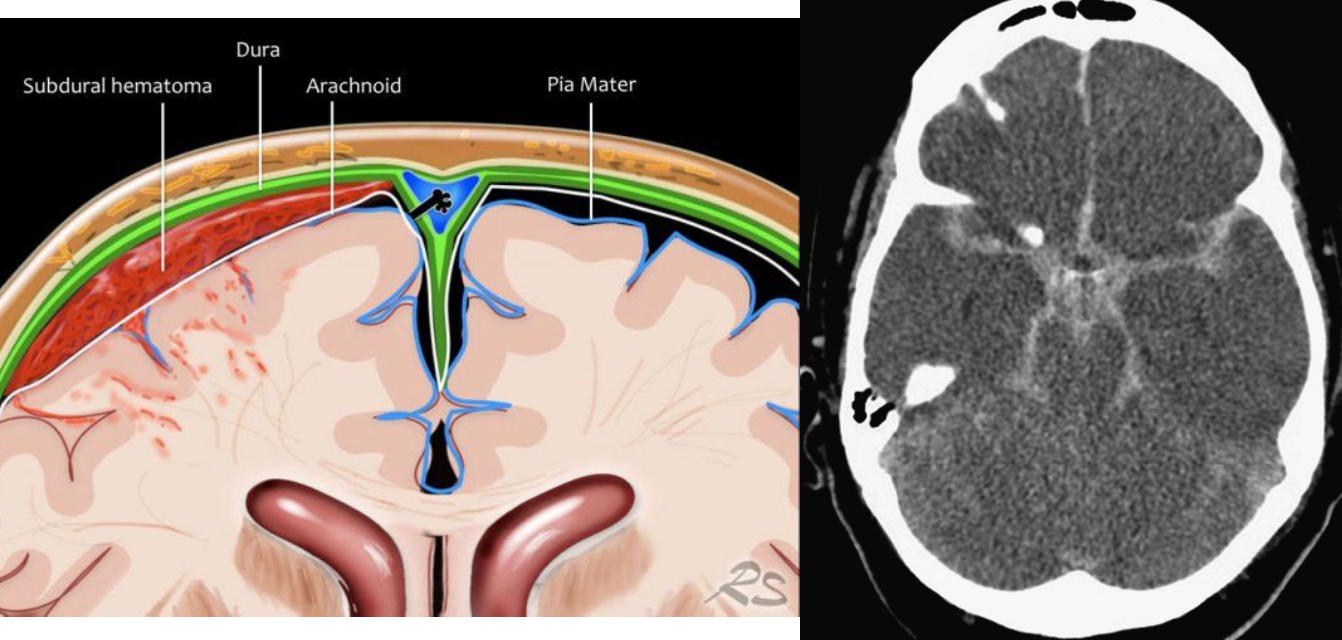

Brain Layers

dura —> thickest and most durable

arachnoid —> thinner than the dura

subdural —> below the dura

subarachnoid —> CSF

pia mater — >adheres to the surface of the brain (soft and fragile) blood supply to the brain

CLOSER TO BRAIN - WORSE DAMAGE

1. Extracerebral hemorrhages-hemorrhages from blood vessels in the meninges or on the surface of the brain (bleeding outside brain).

2. Intracerebral hemorrhages-hemorrhages within brain or brainstem

Extracerebral Hemorrhages

3 types depending on WHERE blood accumulates:

1. Subarachnoid hemorrhage-bleeding between arachnoid and pia. —> closest to the brain/blood supply

2. Subdural hemorrhage-bleeding beneath dura.

3. Epidural hemorrhage-bleeding between dura and skull.

● TBI usual cause of subdural and epidural hemorrhages

● After bleeding stops, left with a hematoma/bruise (subarachnoid, subdural, or epidural)--accumulation of clotted or partially clotted blood in the space created by the hemorrhage.

hematoma causing pressure on the brain temporary